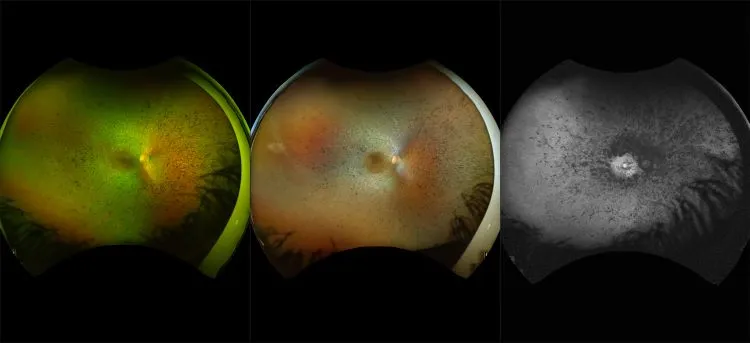

This material is designed as a searchable reference resource to support clinical decision-making. The information contained here should be used as general guidance when viewing optomap and OCT images from Optos devices. The differential diagnosis should be made under the direction of the responsible physician. These images were taken on the latest ultra-widefield optomap devices.

optomap Recognizing Pathology is searchable by pathology and/or optomap image modality. You may search by multiples of each selection. Each individual case is represented by the accompanying thumbnail image. Most cases include several different optomap image modalities. To view a full description of the case, please click on the thumbnail. Each image in the case will be made available through our OptosAdvance software which provides multi-dimensional visualization of digital images to aid in the analysis of anatomy and pathology. Support and pathology definitions can be found by selecting one of the buttons, above. Should you have questions, please complete the form below.